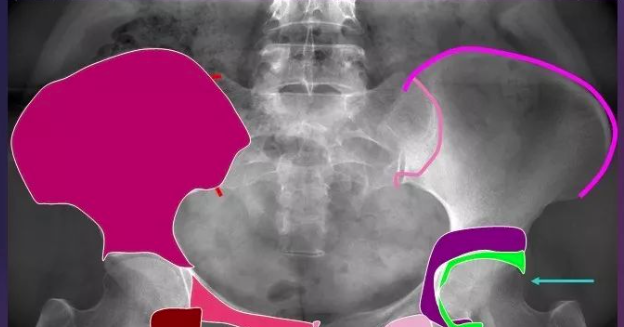

呼盆唤友 骨盆骨折手术专题课程